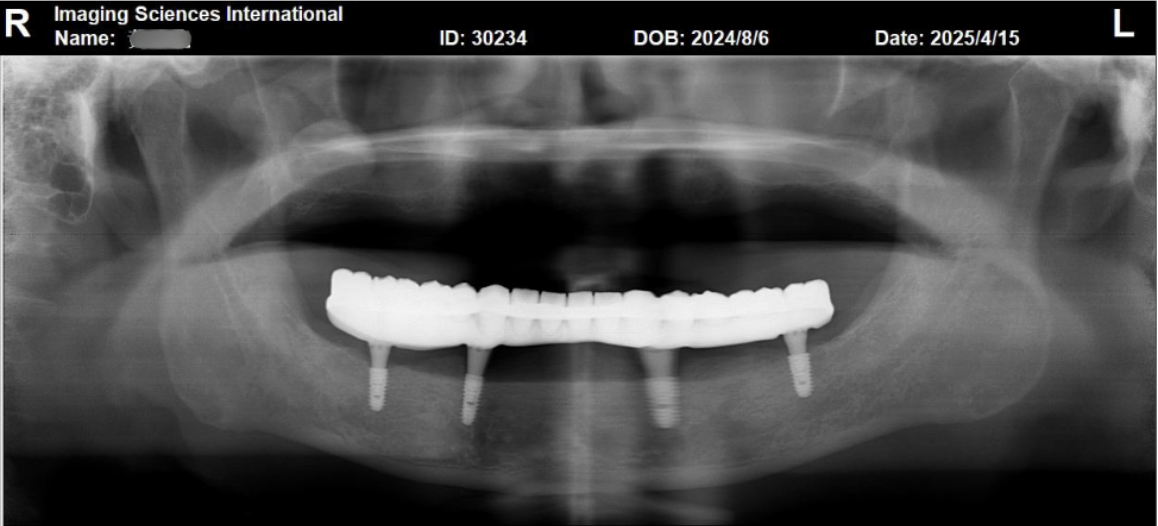

等到植體與齒槽骨完美密合後,醫師便為患者進行支臺齒安裝。從影像顯示(如下圖)能發現,植體周圍骨質已呈現穩定的狀態,可為後續的全口重建打下堅實基礎。

完成支臺齒安裝後1個月,由林錫奎醫師接手,為患者進行全口假牙重建,過程採用高強度金屬支架,能確保假牙在承受咀嚼壓力時不變形。另外,醫師也為患者重新校正了假牙的垂直高度,建立穩定的咬合平衡。(如下圖)